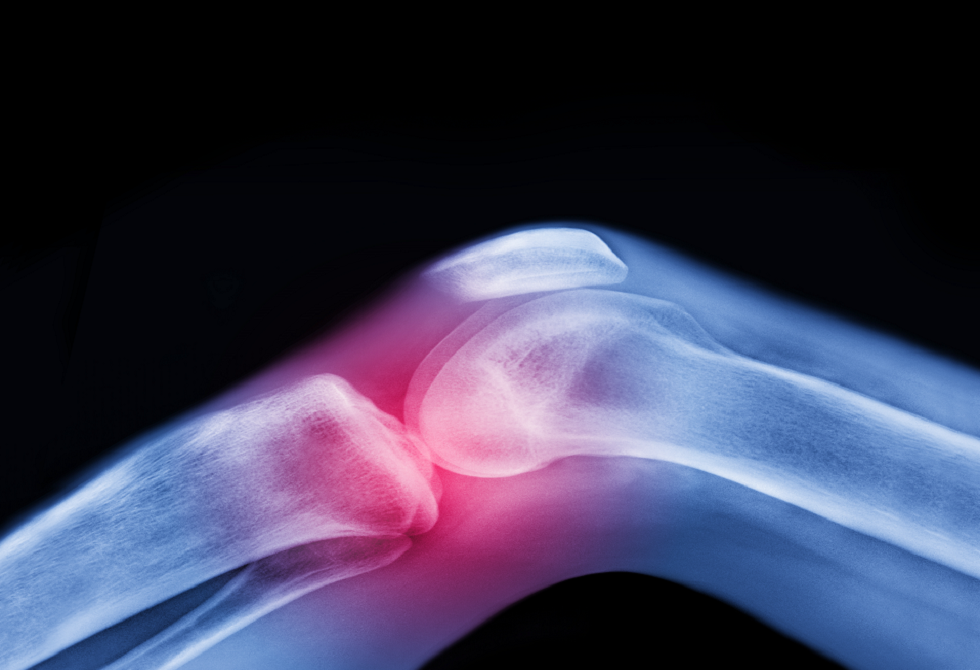

ولا يعتبر الفصال العظمي مجرد تآكل ميكانيكي للمفصل، بل مرضاً يؤثر على جميع مكوناته: السائل الزلالي والغضروف والعظم والأربطة والعضلات المحيطة، وحتى الأعصاب التي تدعم الحركة. وتستهدف الحركة المنتظمة جميع هذه العناصر، وتحافظ على صحة المفصل بكفاءة.

ويفتقر الغضروف، وهو طبقة واقية تغطي أطراف العظام، إلى إمدادات الدم المباشرة ويعتمد على الحركة للبقاء صحيا. فهو يعمل مثل الإسفنجة: ينضغط عند الحركة، فيخرج السوائل ويعيد امتصاص المغذيات، ما يحافظ على مرونة المفصل وصحته.

لذلك، فإن الفكرة التقليدية القائلة بأن الفصال العظمي هو مجرد “تآكل واهتراء” ليست دقيقة. بل هو عملية طويلة من التآكل والإصلاح، حيث تلعب الحركة والتمارين المنتظمة دورا أساسيا في الحفاظ على صحة المفصل.